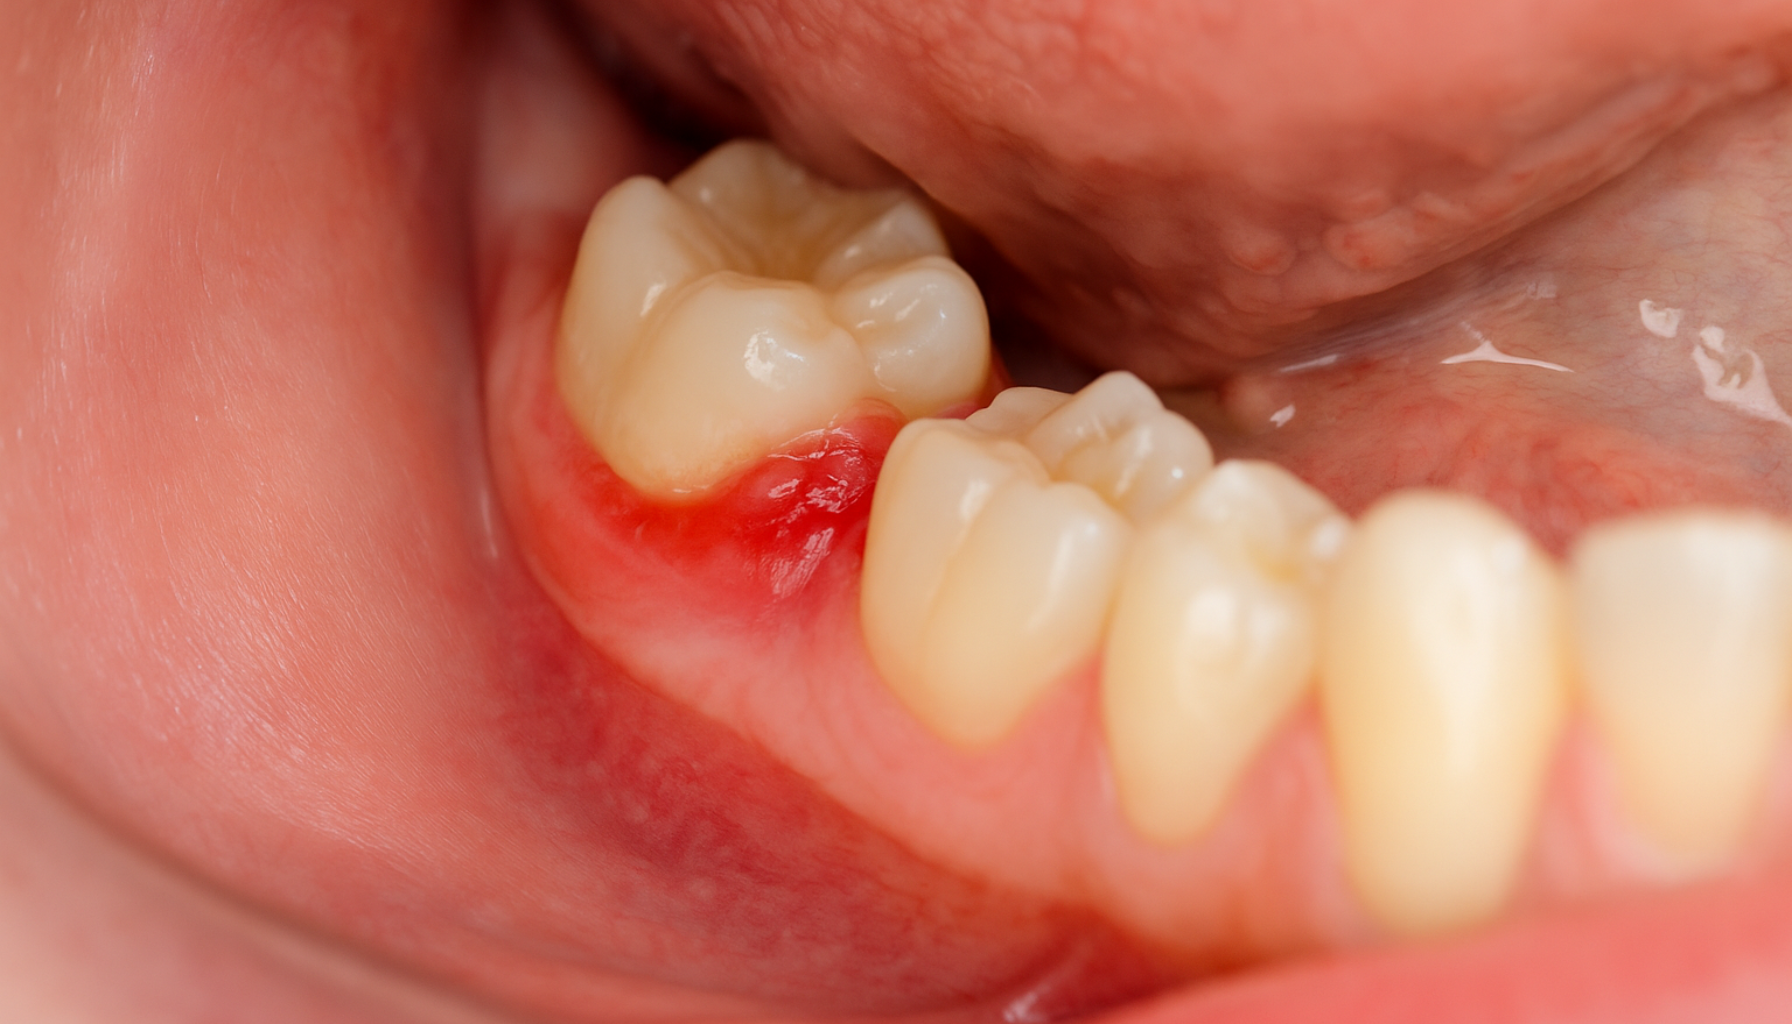

De mest typiske symptomene på perikoronitt er smerter og hevelse rundt visdomstannen. Smerten kan stråle til kjeven, øret eller halsen, og forverres gjerne når man tygger eller åpner munnen. Mange opplever også vansker med å gape helt, noe som kalles trismus.

Andre vanlige tegn er dårlig smak i munnen og vond lukt, som skyldes bakterievekst under tannkjøttlappen. Rødhet, ømhet og blødning i området er også hyppige funn. I mer alvorlige tilfeller kan man få feber, hovne lymfeknuter og generell sykdomsfølelse. Kronisk perikoronitt kan gi mer diffuse plager, med tilbakevendende ømhet og lett hevelse som stadig kommer tilbake. Dette kan være like belastende i lengden som et akutt utbrudd.

Symptomer på perikoronitt bør aldri ignoreres. En ubehandlet infeksjon kan spre seg til andre deler av kroppen og i sjeldne tilfeller gi alvorlige komplikasjoner. Derfor er det viktig å kontakte tannlegen så snart man merker tydelige tegn på betennelse rundt en visdomstann.